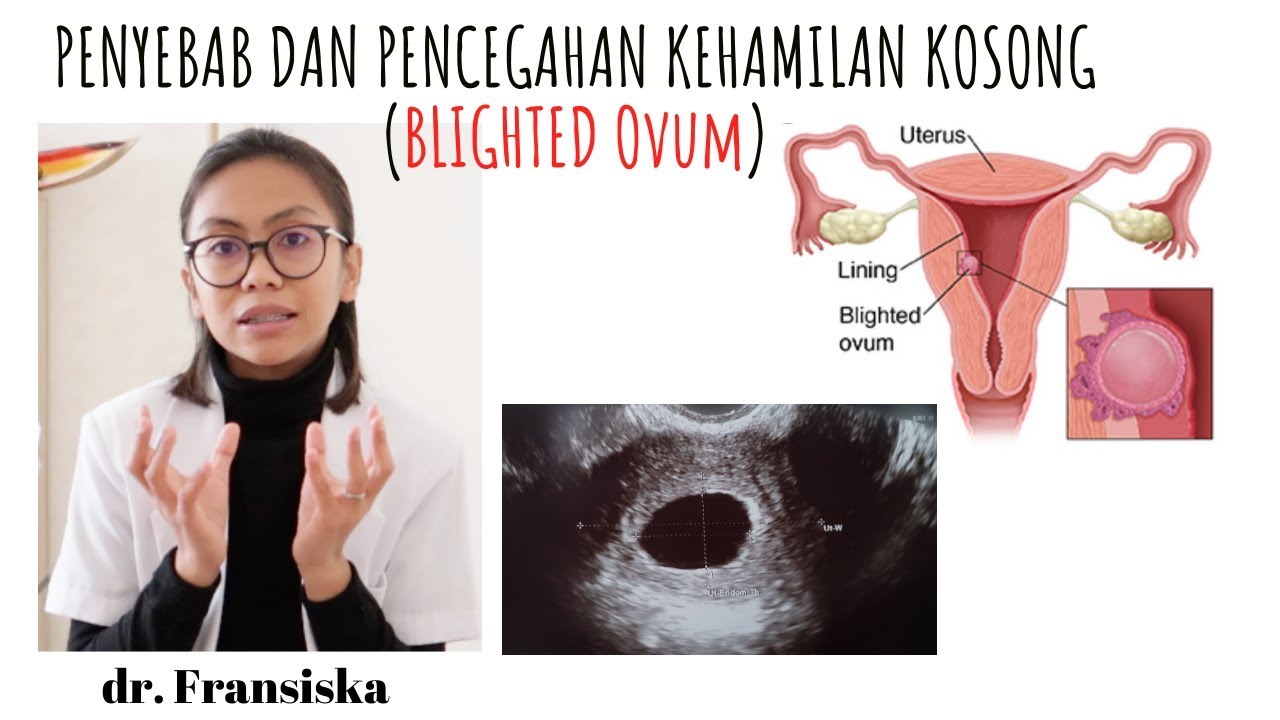

HAMIL KOSONG ATAU BLIGHTED OVUM (BO) | APA PENYEBABNYA DAN PENCEGAHANNYA ? - YouTube

HAMIL KOSONG ATAU BLIGHTED OVUM (BO) | APA PENYEBABNYA DAN PENCEGAHANNYA ? - YouTube